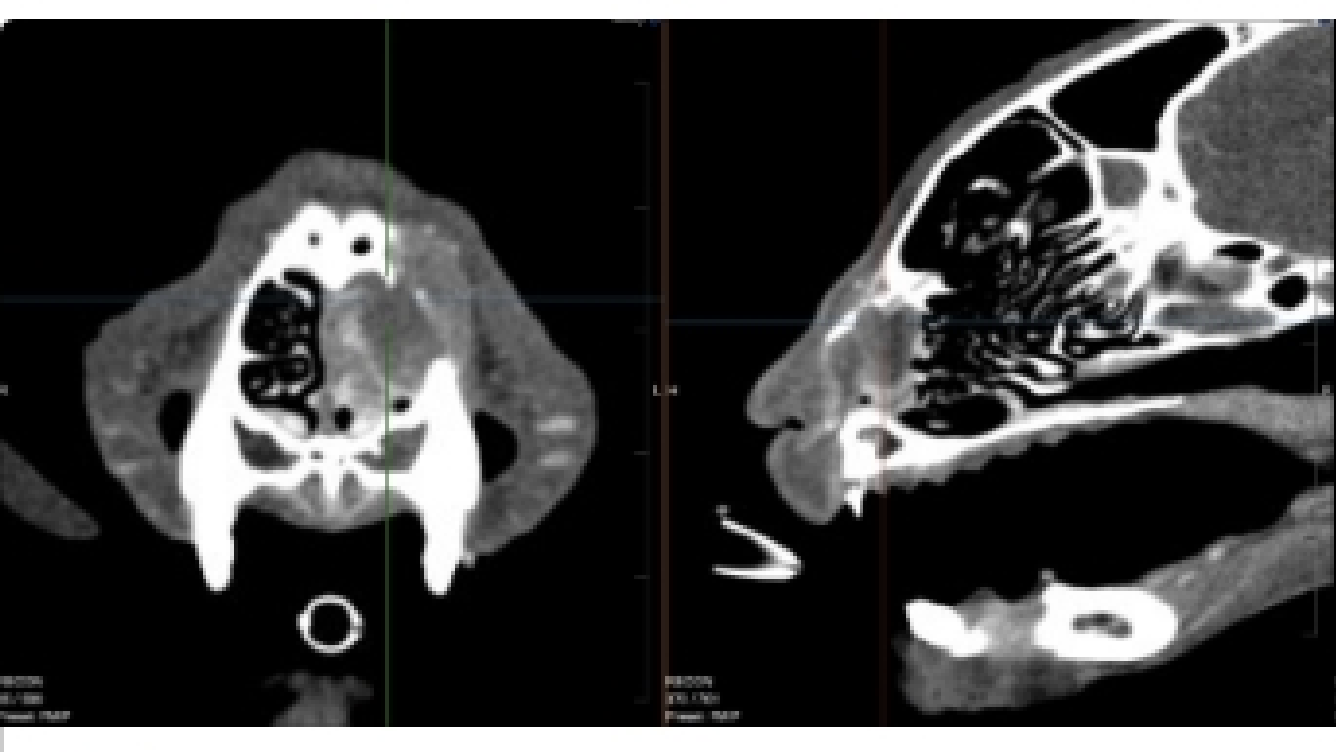

CT (Computed Tomography)

There are many indications for CT scan in animals - such as further evaluation of the nasal cavity, checking for ectopic ureters, finding abnormal vessels, etc.

Cat with a congenital liver shunt